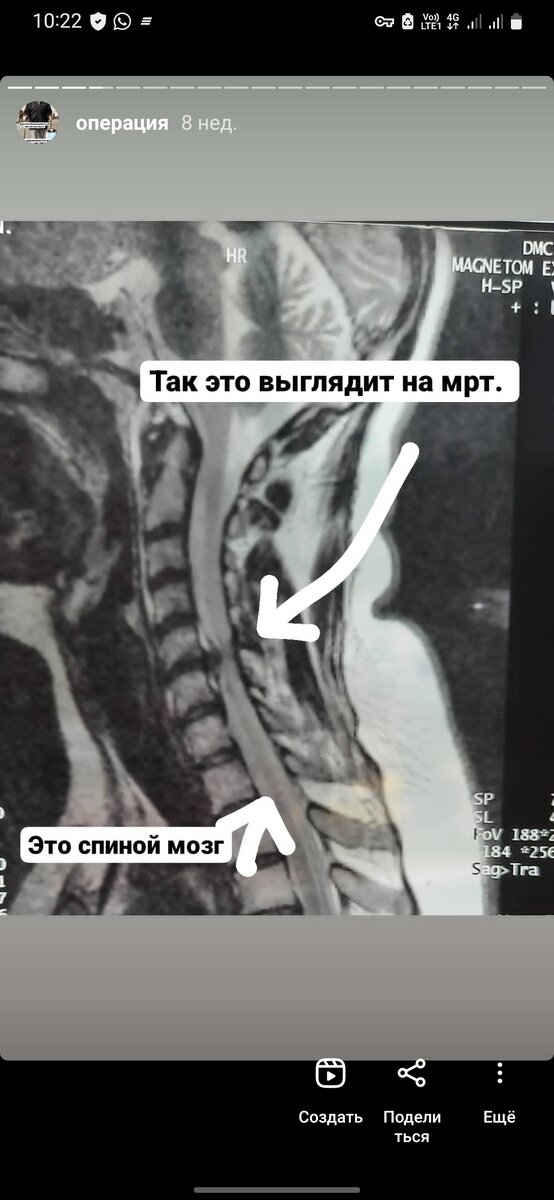

Мой снимок 2017 года во время первого приступа. Грыжа 4 мм между дисками с5-6. Спиной мозг уже прджимает. Продолжение будет.